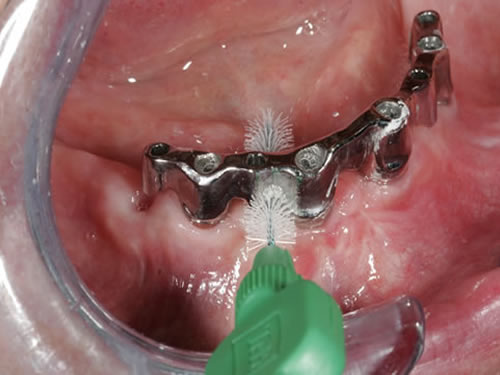

Zusätzlich müssen aber die Pfeiler zwischen den Zahnkronen oder den Stegelementen gesäubert werden. Dazu sind kleine Bürstchen geeignet, die von außen und innen zwischen den Zähnen und Implantaten hindurchgeführt werden (Abb. 9.6 bis 9.9).

Abb. 9.7: Reinigung mit einem Zahnzwischenraumbürsten.